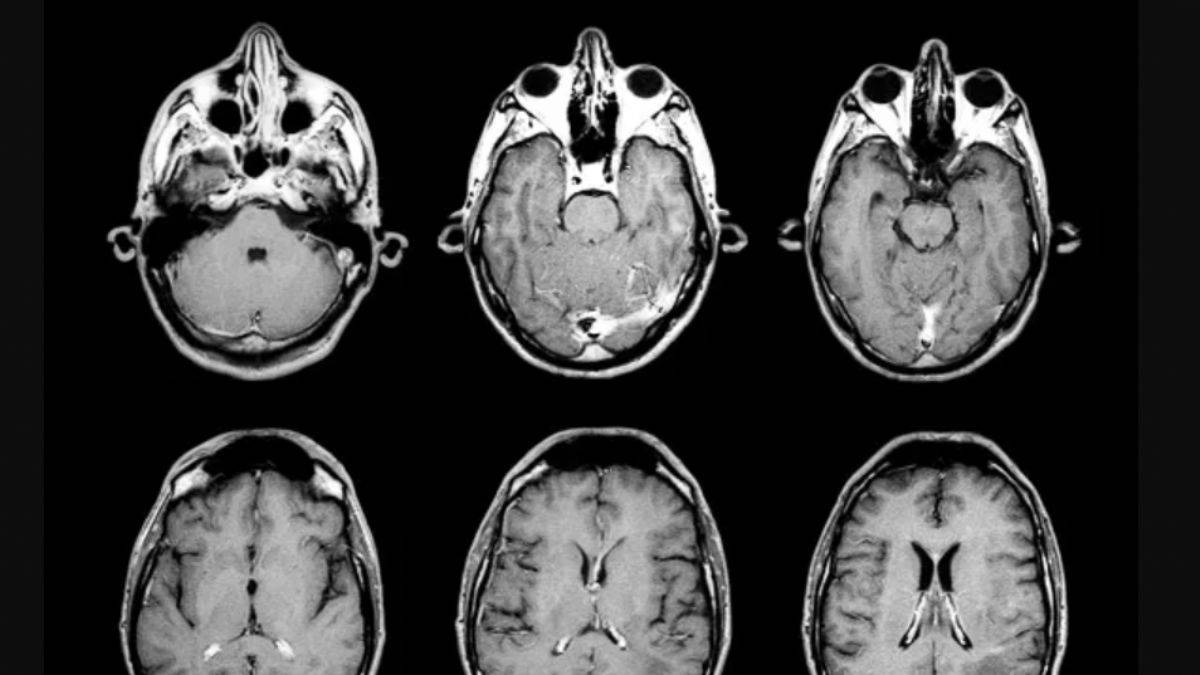

Doktorlara yeni 'beyin ölümü' kılavuzu

ABD'de 4 tıp derneği, doktorlara, beyin ölümünün gerçekleşip gerçekleşmediğine karar verebilmelerine yönelik yeni bir kılavuz hazırladı.

Fotoğraf: Arşiv